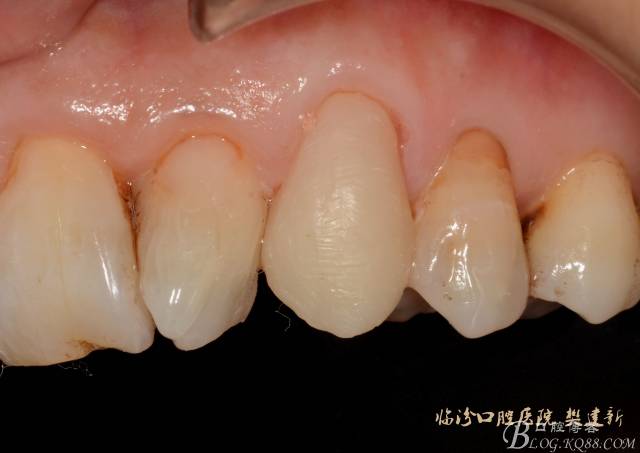

圖10 修復(fù)體代入口內(nèi)照

圖12 修復(fù)體代入口內(nèi)正面照